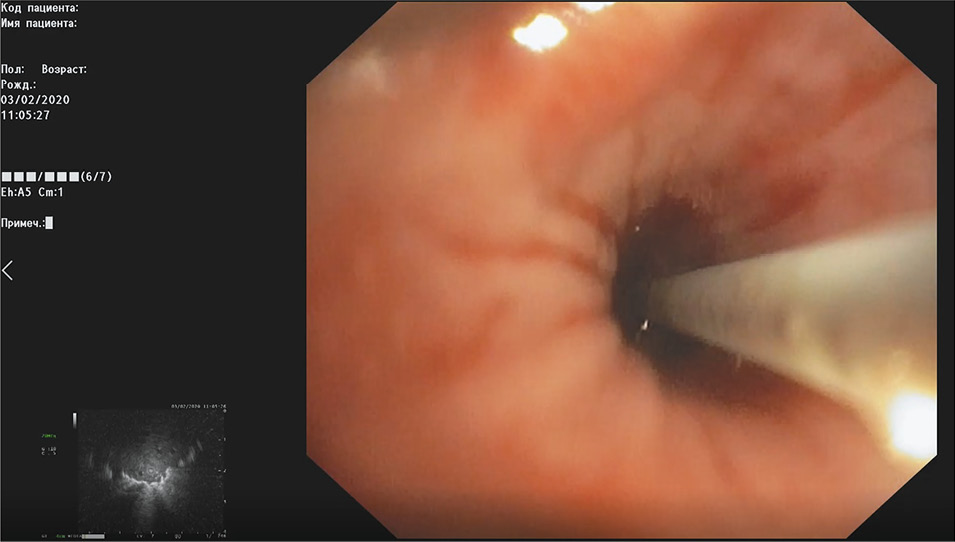

Пациенту осуществляют УЗ-бронхоскопию. С помощью УЗ-зонда, проведенного через инструментальный канал аппарата, производится сканирование сегмента, в котором по данным мультиспиральной КТ органов грудной клетки определяется новообразование (рис. 3).

Рис. 3. Cканирование сегмента, в котором определяется новообразование.